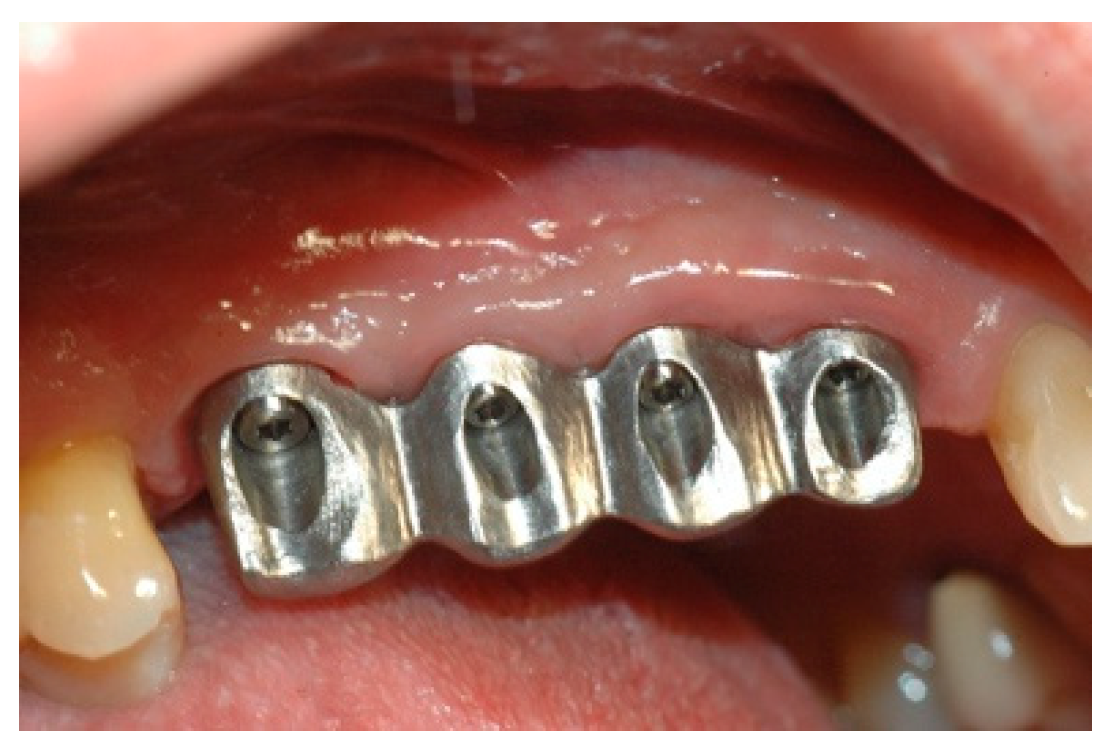

Once the mesostructure was made, it was checked to verify passive adaptation and its precise coupling with the arched fixtures (Figure 8 and Figure 9).

Figure 8. Mesostructure test.

Prosthesis 02 00023 g008

Figure 9. Mesostructure test.

Prosthesis 02 00023 g009